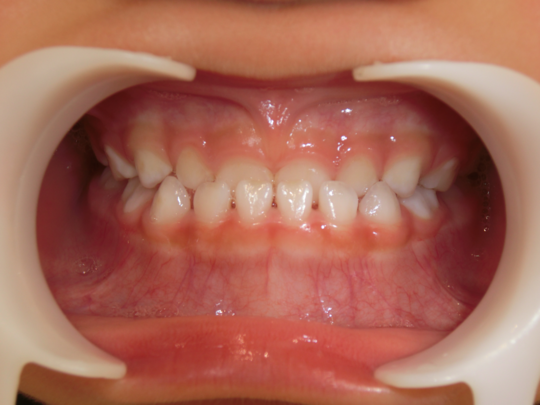

治療後

治療の副作用(リスク)歯の動き方には個人差があり、予想された治療期間が延長する可能性があります。。床矯正の使用状況、矯正歯科治療には患者さんの協力が必要であり、それらが治療結果や治療期間に影響します。2次矯正が必要になる場合もあります。